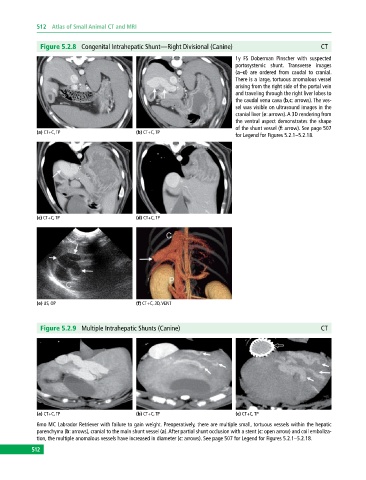

Figure 5.2.8 Congenital Intrahepatic Shunt—Right Divisional (Canine) CT

1y FS Doberman Pinscher with suspected

portosystemic shunt. Transverse images

(a–d) are ordered from caudal to cranial.

There is a large, tortuous anomalous vessel

arising from the right side of the portal vein

and traveling through the right liver lobes to

the caudal vena cava (b,c: arrows). The ves-

sel was visible on ultrasound images in the

cranial liver (e: arrows). A 3D rendering from

the ventral aspect demonstrates the shape

of the shunt vessel (f: arrow). See page 507

(a) CT+C, TP (b) CT+C, TP

for Legend for Figures 5.2.1–5.2.18.

(c) CT+C, TP (d) CT+C, TP

(e) US, OP (f) CT+C, 3D, VENT

Figure 5.2.9 Multiple Intrahepatic Shunts (Canine) CT

(a) CT+C, TP (b) CT+C, TP (c) CT+C, TP

6mo MC Labrador Retriever with failure to gain weight. Preoperatively, there are multiple small, tortuous vessels within the hepatic

parenchyma (b: arrows), cranial to the main shunt vessel (a). After partial shunt occlusion with a stent (c: open arrow) and coil emboliza-

tion, the multiple anomalous vessels have increased in diameter (c: arrows). See page 507 for Legend for Figures 5.2.1–5.2.18.